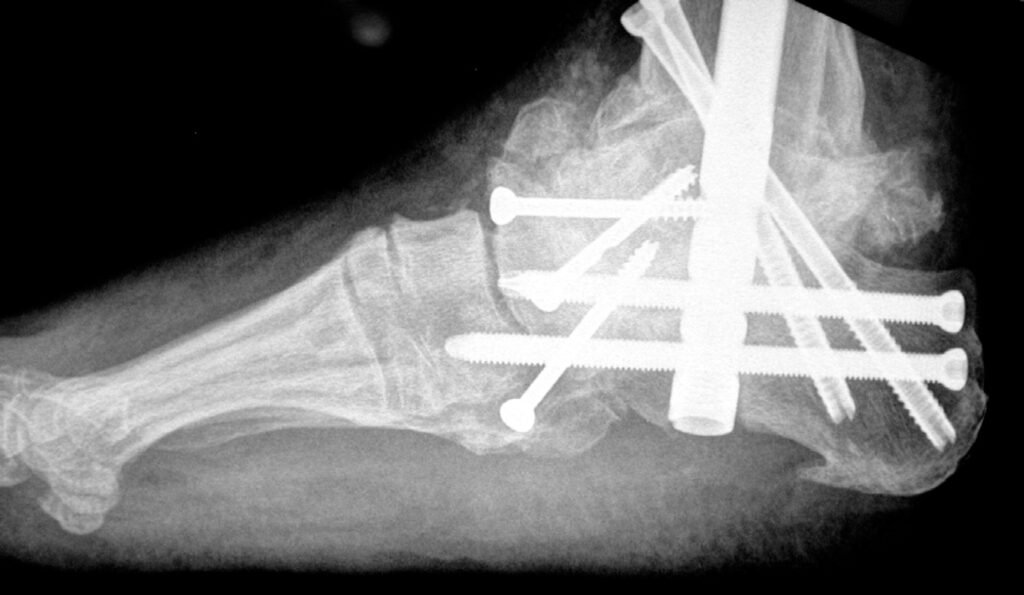

• Metal plates, screws, or rods may be used to hold the bones in place while they heal.